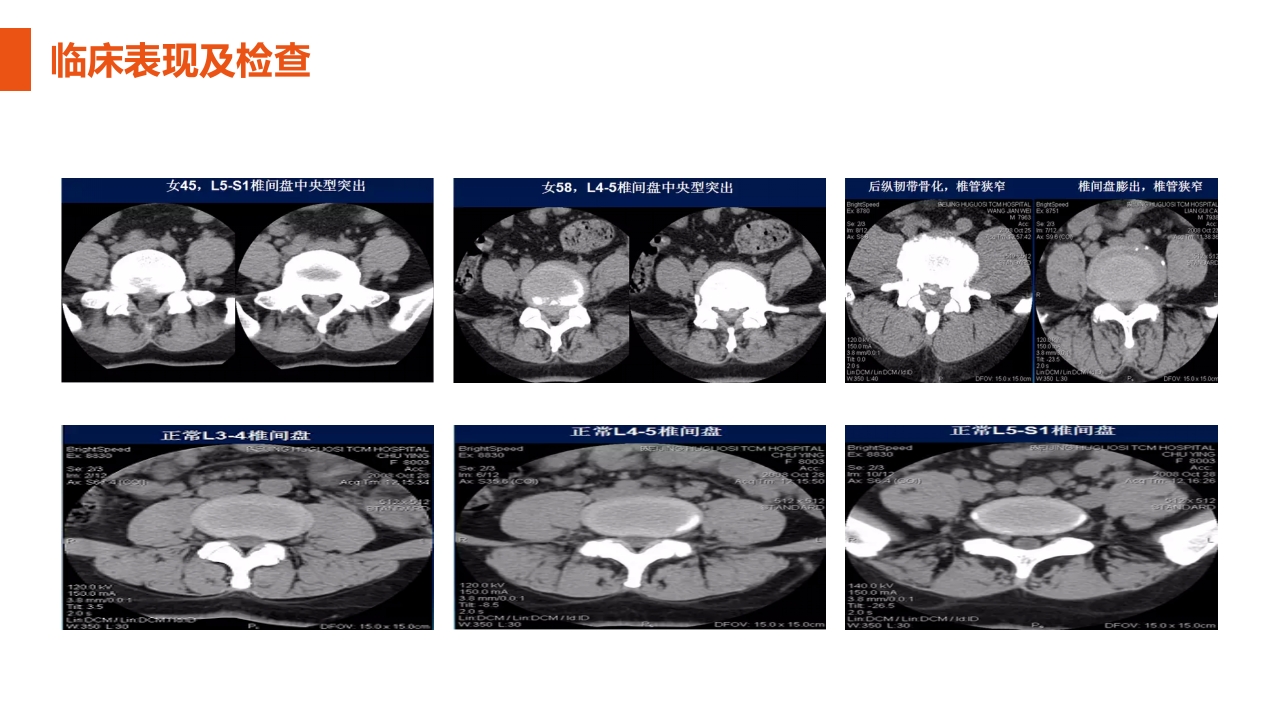

汇报人:xxx 目录 CONTENTS 01 概述及解剖概要 02 病因及易发群体 03 临床表现及检查 04 常见压痛点 05 症状的治疗 PART 01 概述及解剖概要 概述及解剖概要 腰椎间盘突出症的概述: 腰椎间盘突出症是临床上较为常见的腰部疾病之一。 主要是因为腰椎间盘各组份(髓核、纤维环及软骨板), 尤其是髓核,发生不同程度的退行性病变后,在外界因 素的作用下,椎间盘的纤维环破裂,髓核组织从破裂之 处突出(或脱出)于后侧方椎管内,从而导致相邻的组 织,如脊神经根和(或)脊髓等受到刺激或压迫,产生 腰痛,一侧下肢或双下肢麻木、疼痛等一系列临床症状。 严重可引起下肢瘫痪。 概述及解剖概要 腰椎解剖概要 : 腰部椎骨 概述及解剖概要 腰椎解剖概要 : 腰椎椎间盘 组成:外部纤维...